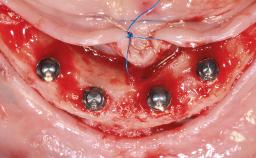

Fully Guided and Minimally Invasive Implant Placement as the Basis for Effective Digital Fabrication of a Tapered-Crown Full-Arch Prosthesis

A 74-year-old male patient presented to the Department of Oral Medicine at the Goethe University in Frankfurt, Germany. The patient had been edentulous for 15 months and had been treated with a complete denture by students in the undergraduate program. During a recall appointment, the patient complained of poor retention of his maxillary complete denture. The prosthetic site consisted of a rigid and thick maxillary ridge with an undercut in the left posterior region. The prosthesis covered the entire palate and was dislodged by biting on solid foods such as apples. The patient did not have high esthetic expectations, but he did want improved chewing comfort and "fixed teeth".